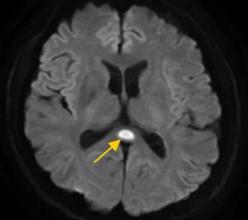

所以他立即到医院就诊,并被转移到神经内科。经一系列检查,医生诊断为:可逆性邈体压部综合征。

什么是“可逆性体压部综合征”?医生解释说,如果把大脑比作一个城市,体压部就是连接左右脑的“跨海大桥”,体压部就是桥上的“核心枢纽”。当它因为乙醇、熬夜或感染而“肿胀”时,大脑信号会“堵塞”,导致一系列“故障”。

根据董先生大脑的图像数据,受压部位发生病变。

因此,董先生会出现视力模糊、看不清东西等问题。除了“压力部分”之外,松子的其他部分也有病变,所以小董会出现幻听、手抖等症状。简单来说就是“脑子喝坏了”。①